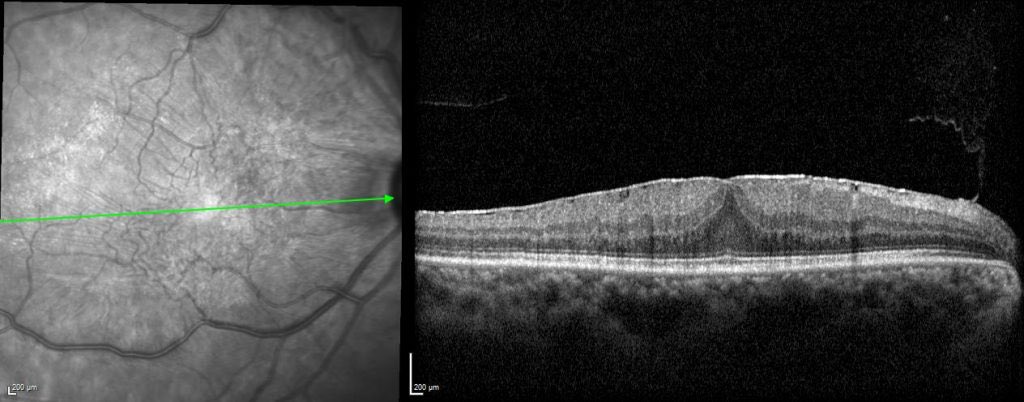

غشاء فوق #الشبكية

هو عشاء ينمو على سطح الشبكية في منطقة مركز الابصار (فوڤيا) وقد يؤثر على الابصار او يسبب في (تموّج) في مركز الابصار

التشخيص يكون كلينيكي مع اجراء تصوير طبقي لشبكية العين Opictal coherence tomography